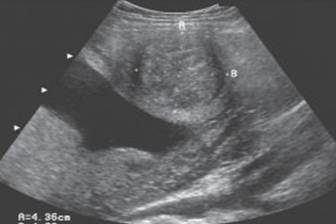

Anterior uterine fibroid